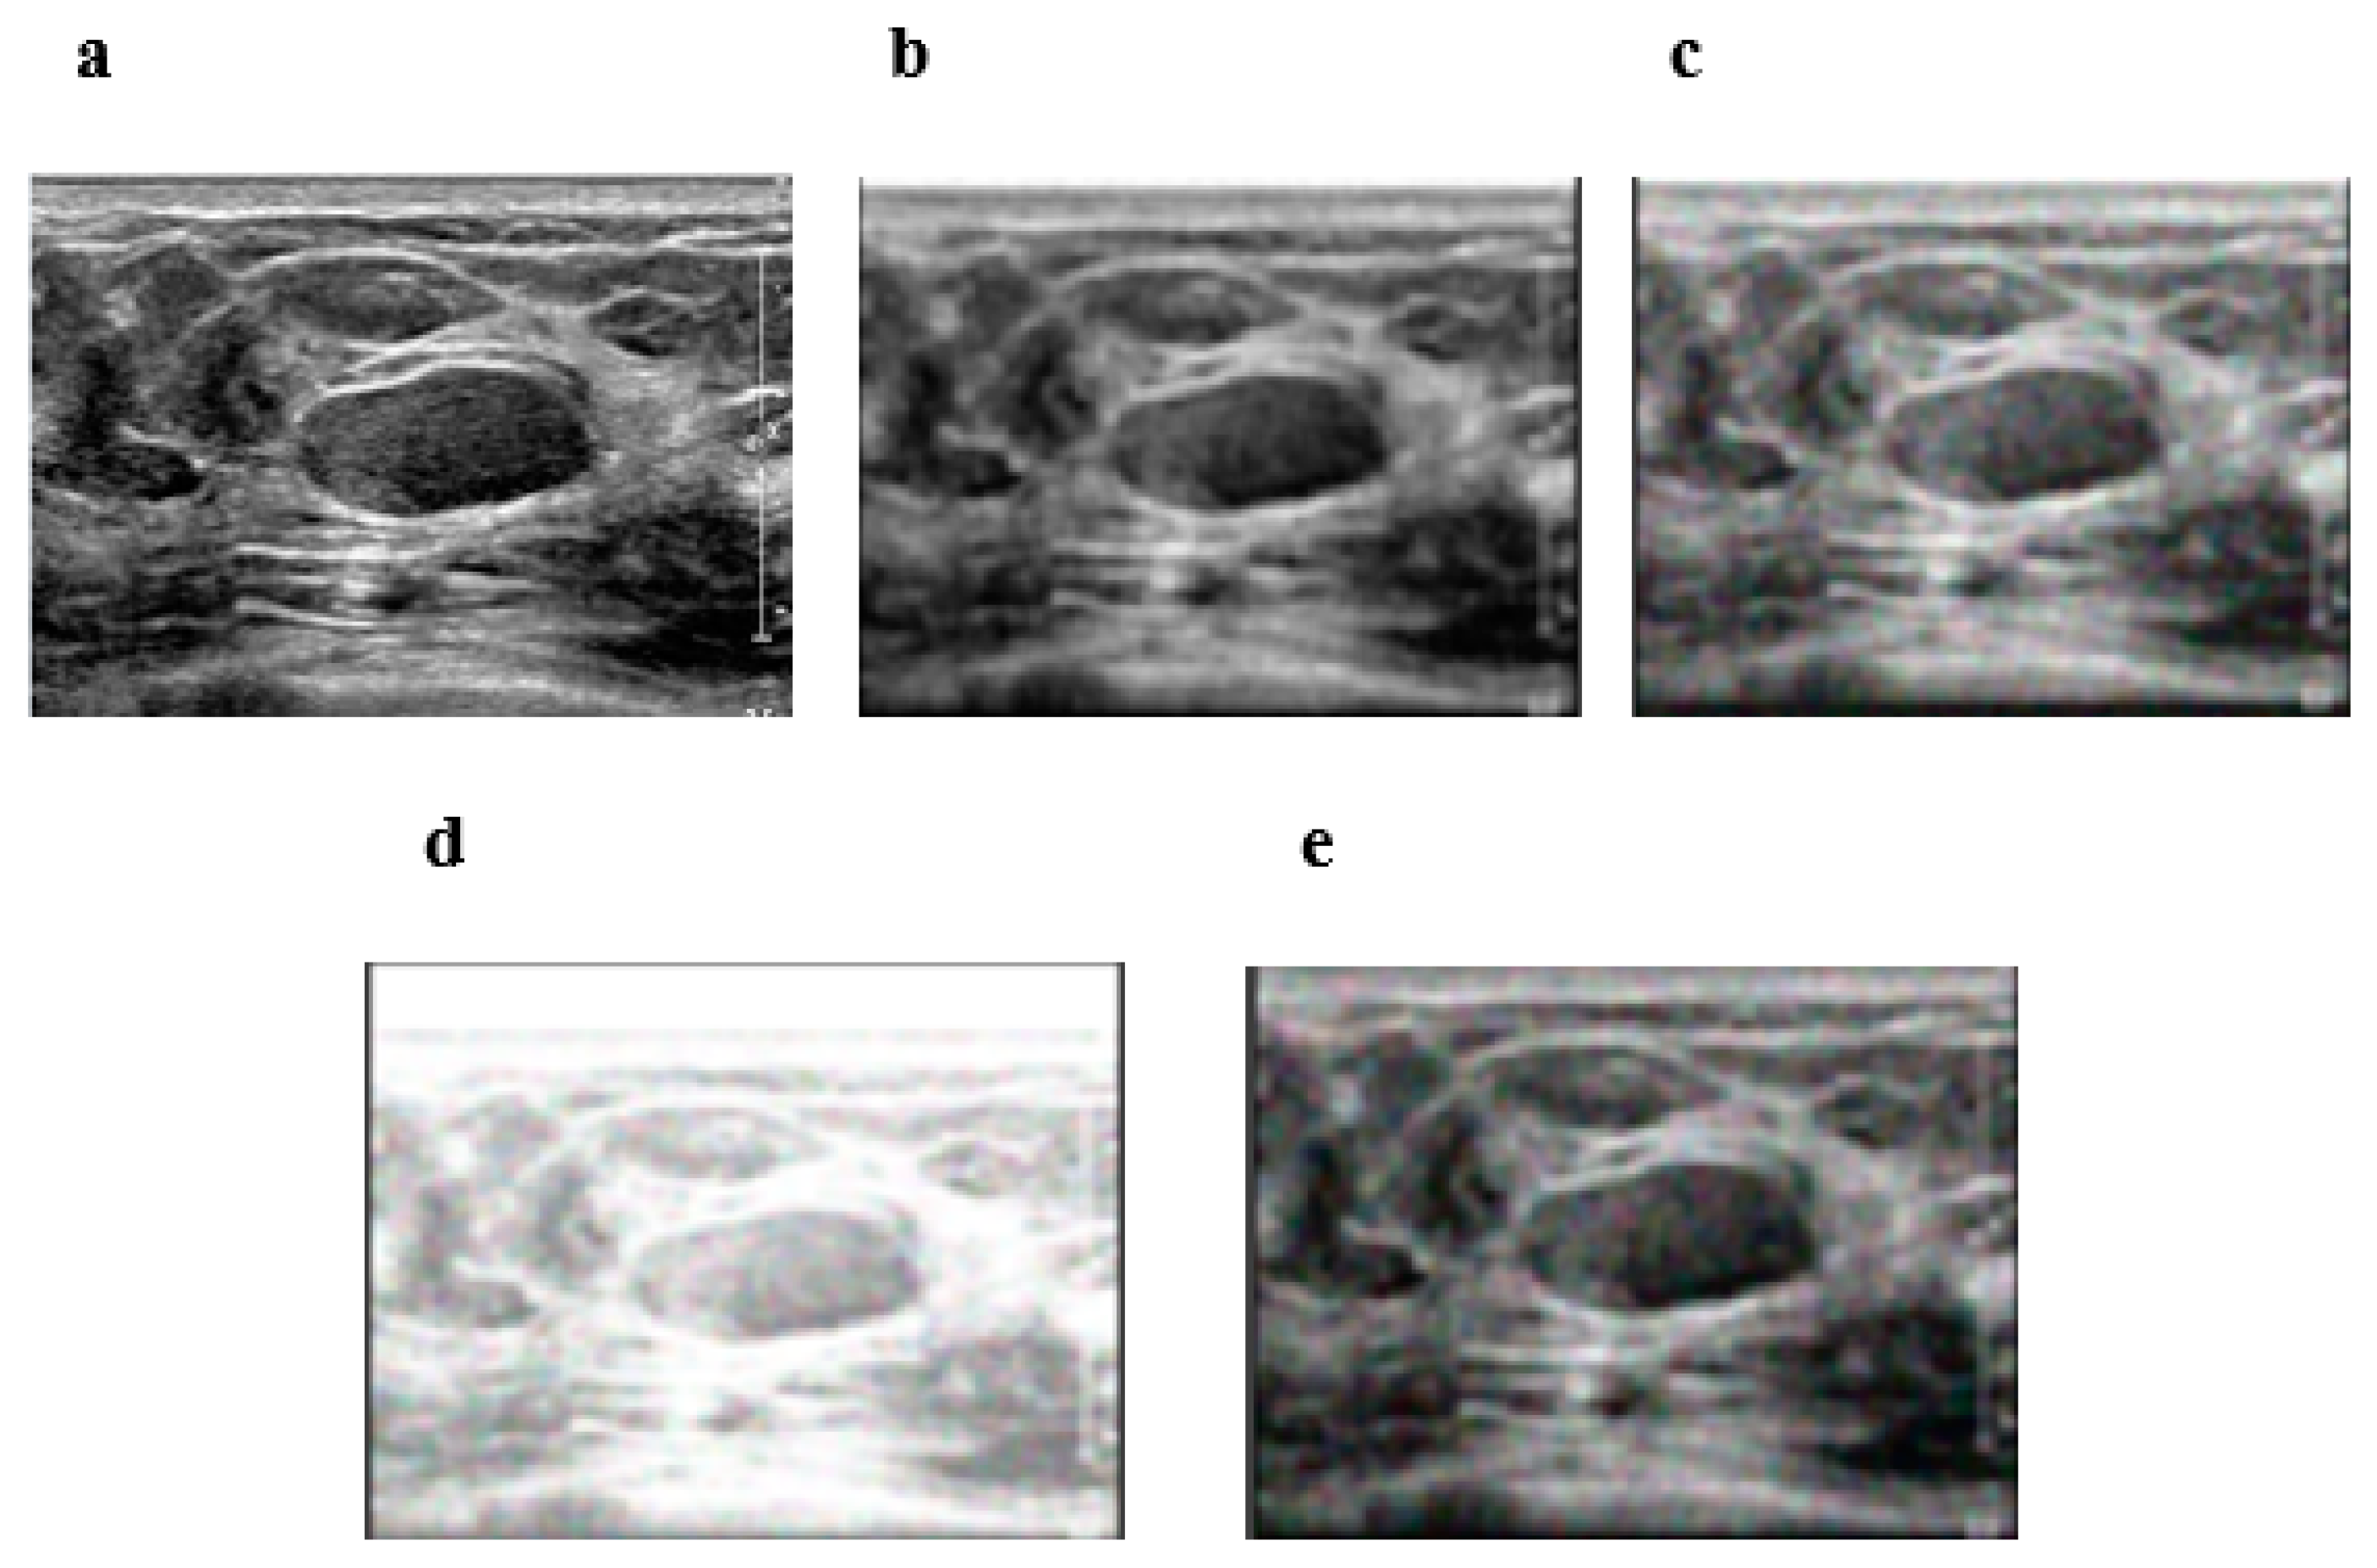

3.1. Private Dataset Image Results

3.2. Private Dataset Image Results